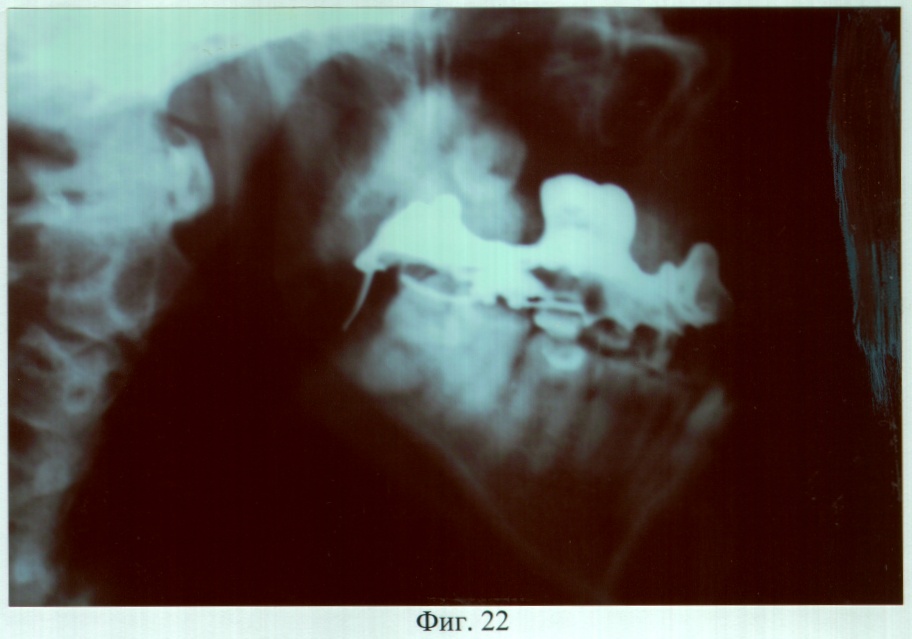

На фиг.22 – рентгенограмма больной С. через 3 года после ортопедического лечения (правая латеральная проекция).

Адаптация к протезу наступила в течение семи дней, после чего больная отмечала удовлетворительное функциональное состояние зубочелюстного аппарата. Фонетическое обследование показало, что до ортопедического лечения нарушено произношение звуков – г, ж, к, п, р, т, ц, ч; k=5; U=21,3%. После протезирования нарушено произношение звуков – г, ж, к, р, ц; k=3; U=6,6%. При осмотре через 3 года больная жалоб не предъявляла, состояние протеза удовлетворительное. Морфологические исследования слизистой оболочки протезного ложа и рентгенография костей лицевого скелета, проведенные до и через 6, 12, 24 и 36 месяцев после протезирования, показали отсутствие признаков воспаления и прогрессирования атрофии.